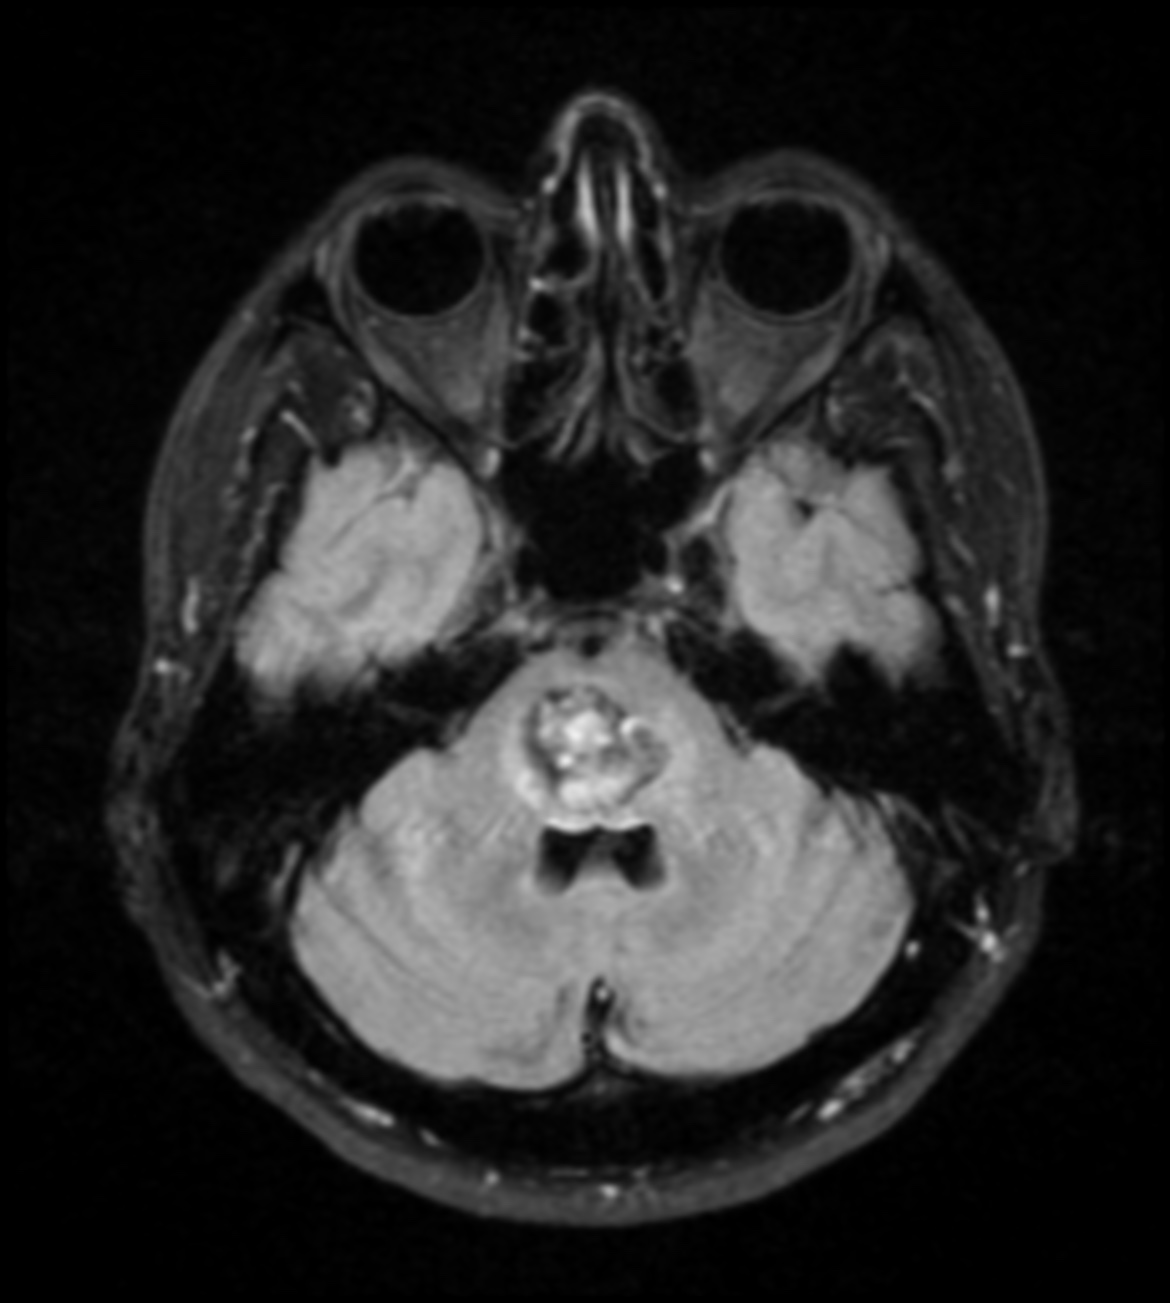

- Magnetic resonance imaging (MRI) is the most sensitive test for identifying cavernous angioma lesions. MRI scans often show small areas of new or old hemorrhages as a rim around the cavernous angioma. These lesions are not visible in cerebral angiography.